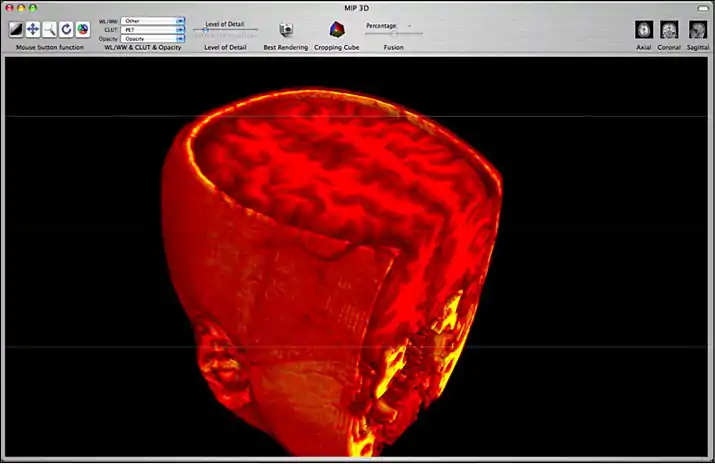

1) Maximum Intensity Projection (MIP)

3D MIP Reconstruction

This reconstruction uses a ‘ray-tracing’ technique to identify which pixel has the maximum intensity on each ray. This technique is useful for contrast MRIs or CTs, and bone CTs.